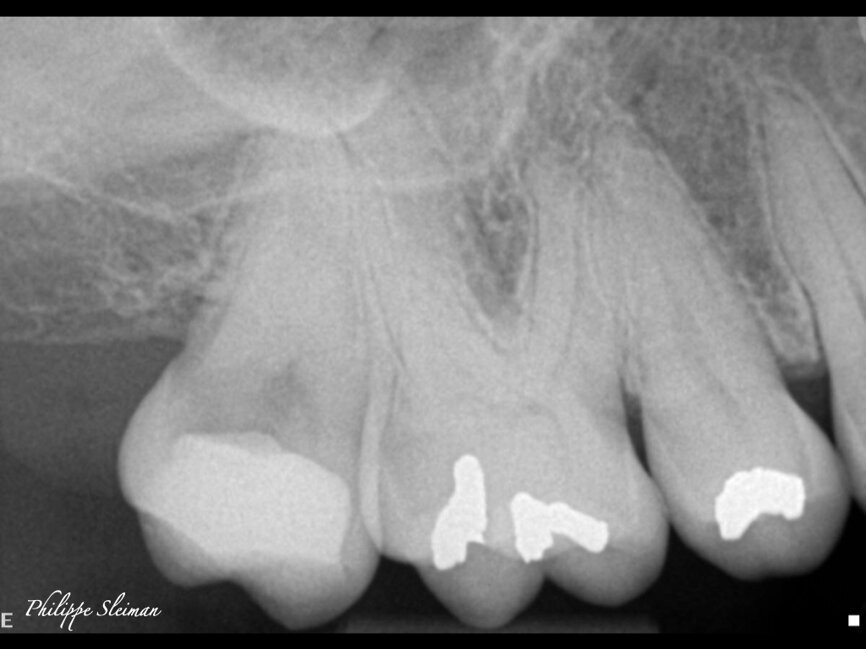

The preoperative radiograph and access cavity under the operating microscope (Images: Philippe Sleiman)

The preoperative radiograph (Fig. 1) revealed that the roots had an uncommon shape, particularly regarding the palatal root, the periodontal ligament and the apex of the mesial root. Upon creating the access cavity (Fig. 2), under the operating microscope, I noticed bleeding from the mesiopalatal angle. Extending the access cavity to that side led to the discovery of a separate canal, which may have been a second palatal or an independent mesial canal.